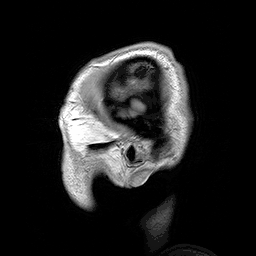

Computed tomography (CT) or Computed Axial Tomography (CAT) scanning uses a series of x-rays of the head taken from many different directions. Typically used for quickly viewing brain injuries, CT scanning uses a computer program that performs a numerical integral calculation (the inverse Radon transform) on the measured x-ray series to estimate how much of an x-ray beam is absorbed in a small volume of the brain. Typically the information is presented as cross-sections of the brain.[12]